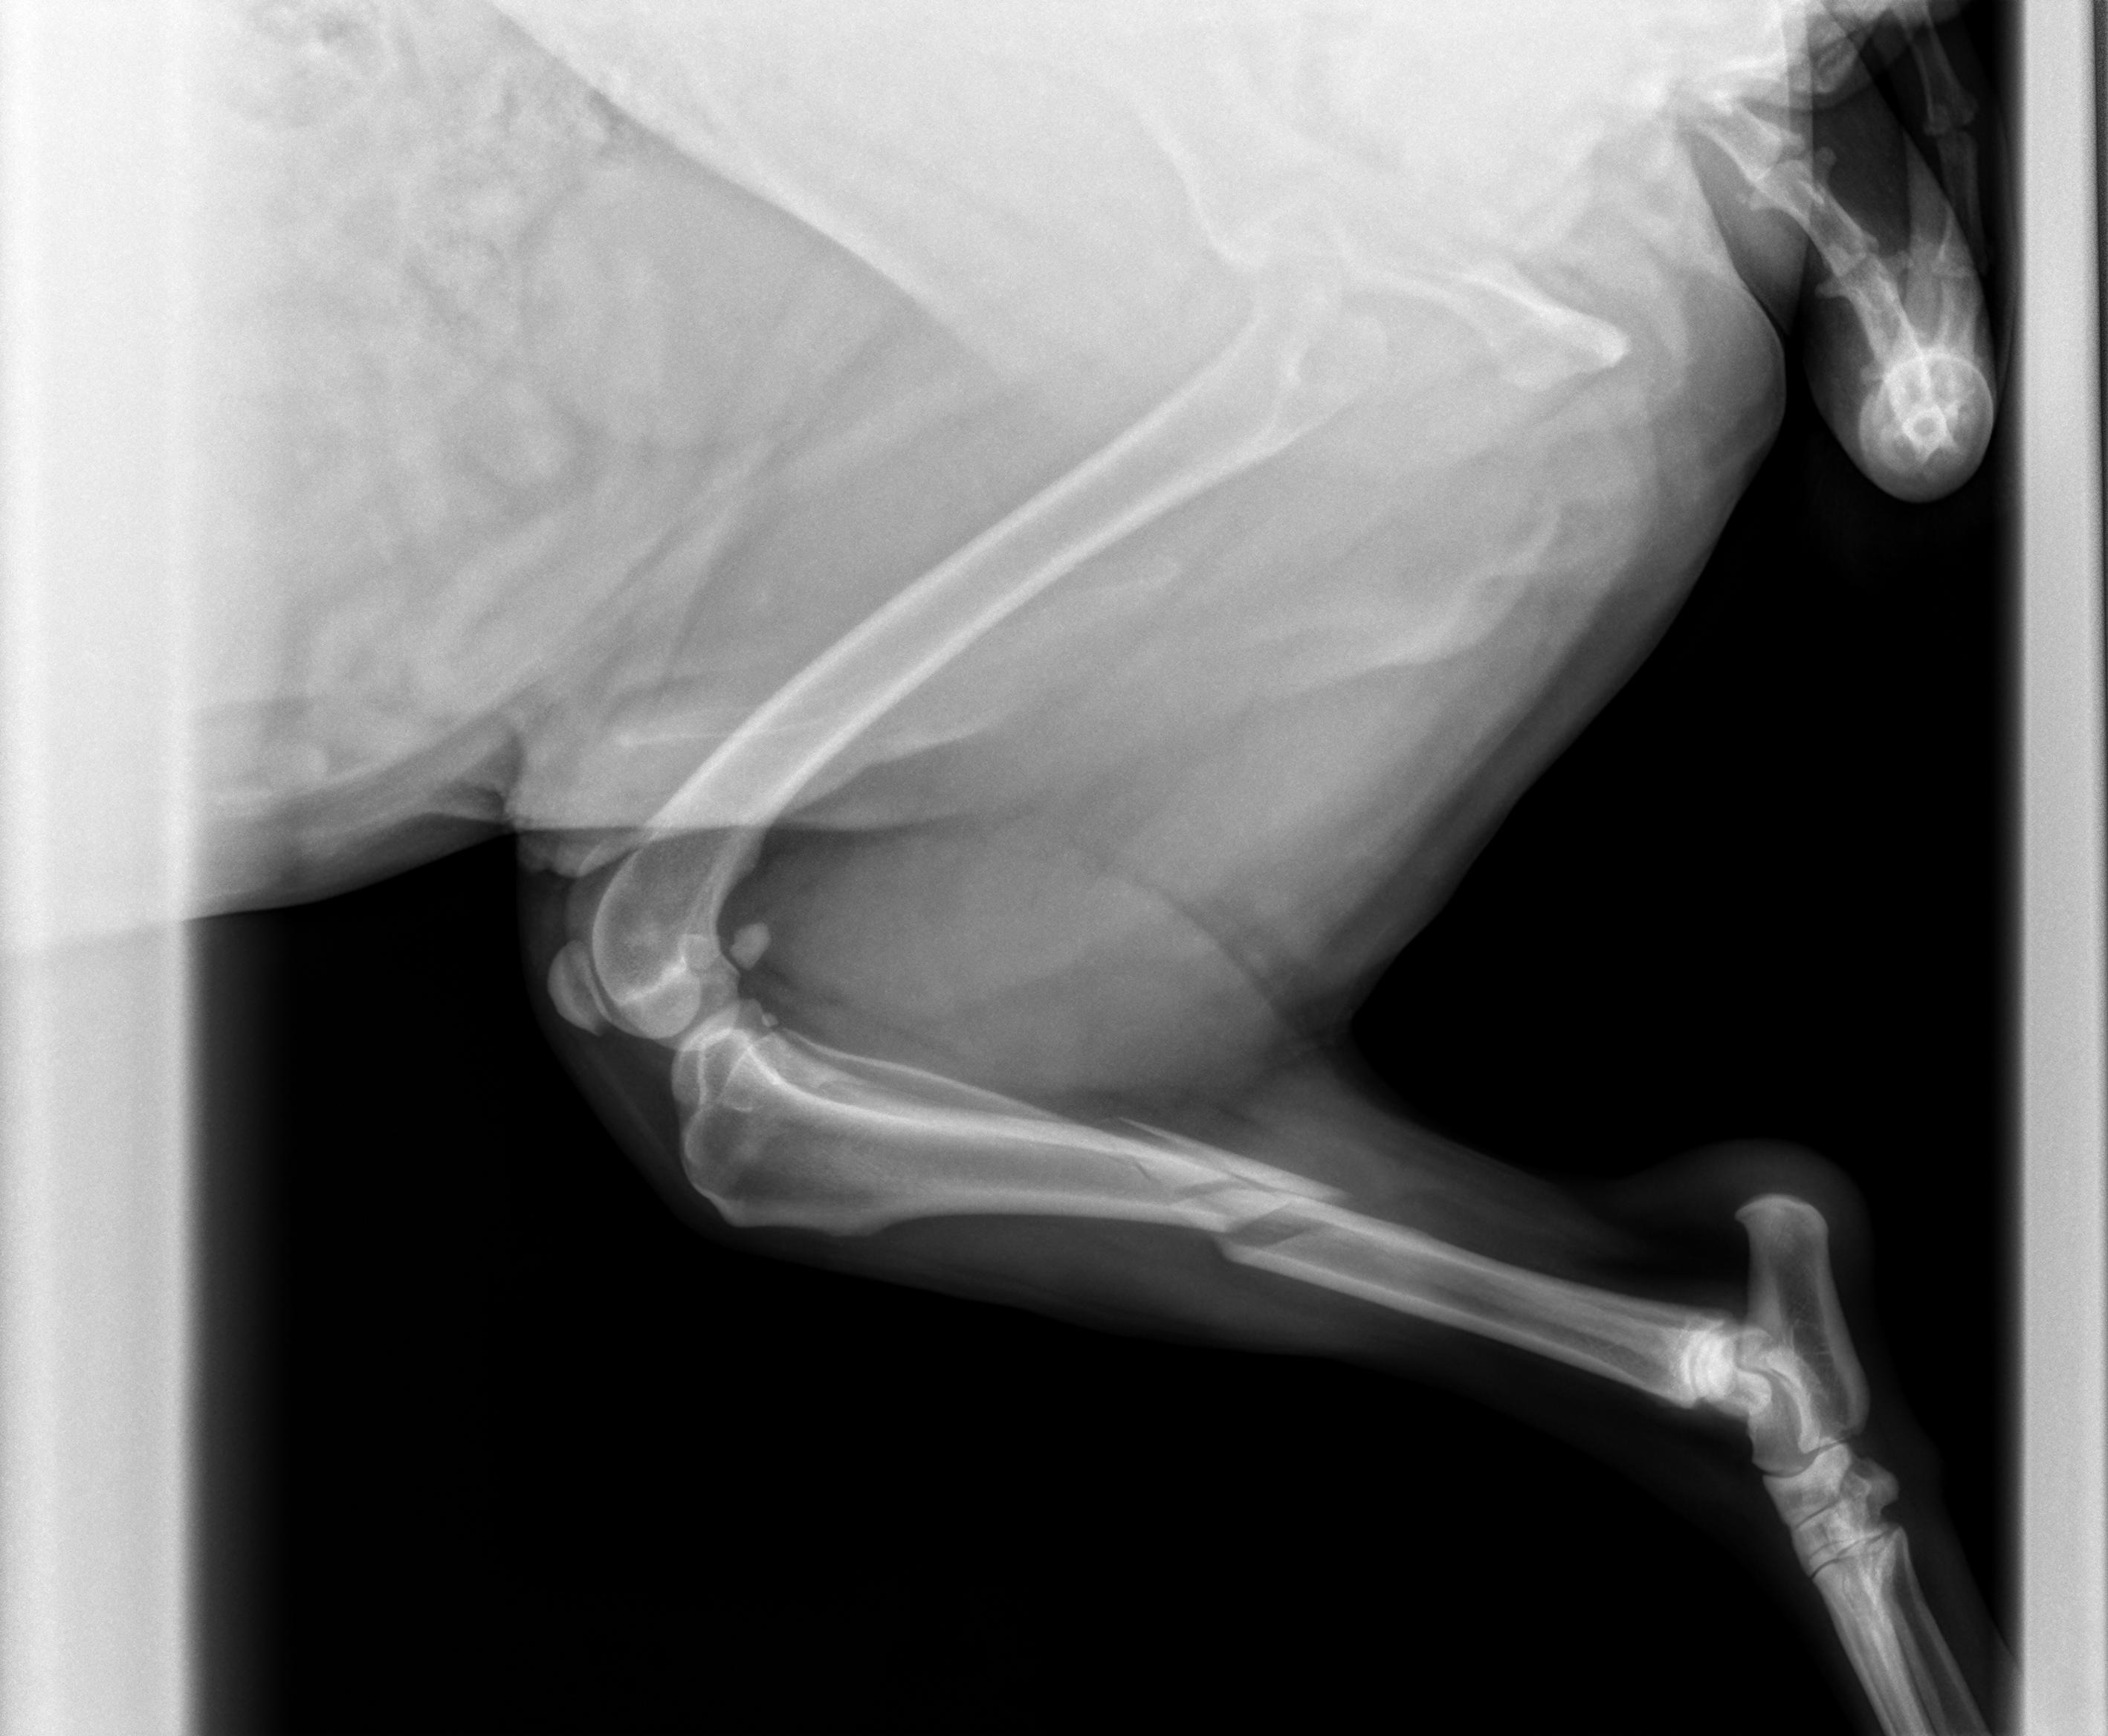

My sweet 6-year-old boy, Kylo, broke both bones in his back leg on Sunday while playing with his sister. The only way for it to heal properly is with surgery — without it, he’ll be in constant pain. Otherwise we'd have to amputate.

We were lucky to find a vet willing to work with us, and his surgery to repair it is scheduled for Friday, October 3rd. The estimate is $3,142–$4,220, plus $888 for his emergency visit. Recovery will take about 8 weeks, with additional costs for pain meds, follow-up visits, and gas to appointments. Altogether, we’re expecting about $6,000 in expenses.